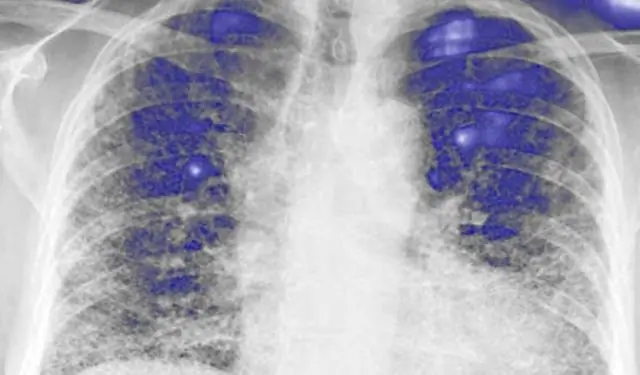

Идиопатический легочный фиброз (IPF) представляет собой интерстициальное заболевание легких, связанное с высокой заболеваемостью и смертностью. Эффективное лечение IPF ограничено. В нескольких недавних исследованиях были исследованы новые терапевтические агенты для IPF, но очень немногие из них рассматривали их сравнительные преимущества и вред.

Идиопатический легочный фиброз (IPF) - это прогрессирующая интерстициальная пневмония неизвестной причины, которая обычно поражает пожилых людей и связана со средней выживаемостью через 3-5 лет после постановки диагноза (1, 2). Диагностические критерии, клинические характеристики и естественное течение заболевания были четко определены в последних научно обоснованных руководствах по диагностике и лечению IPF (2). IPF проявляется в ухудшении одышки и высокой степени заболеваемости пациентов (1). Пациенты с IPF часто испытывают постепенное снижение параметров теста функции легких (PFT) и клинических симптомов, а острые обострения связаны с повышением смертности. До недавнего времени, несмотря на растущее число клинических испытаний, никакое вмешательство, кроме трансплантации легких, не продемонстрировало повышенную выживаемость у пациентов с IPF (2). Тем не менее, недавние крупномасштабные рандомизированные контролируемые исследования (РКИ) нескольких новых препаратов продемонстрировали снижение скорости прогрессирования заболевания, измеряемой с помощью принудительной жизненной емкости (FVC), у четко определенных пациентов с IPF (3-5).